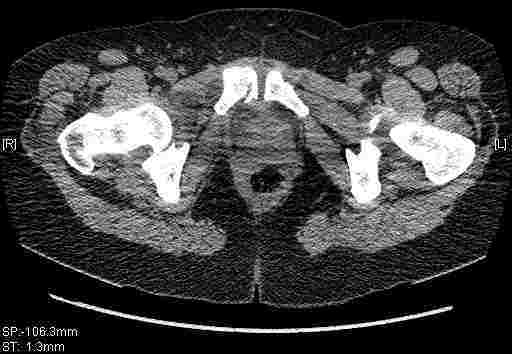

Re: Т-образный перелом вертлужной впадины

Удалось сегодня вывести пациентку в соседнюю больницу, где есть кт. Срезы сделаны только горизонтальные.